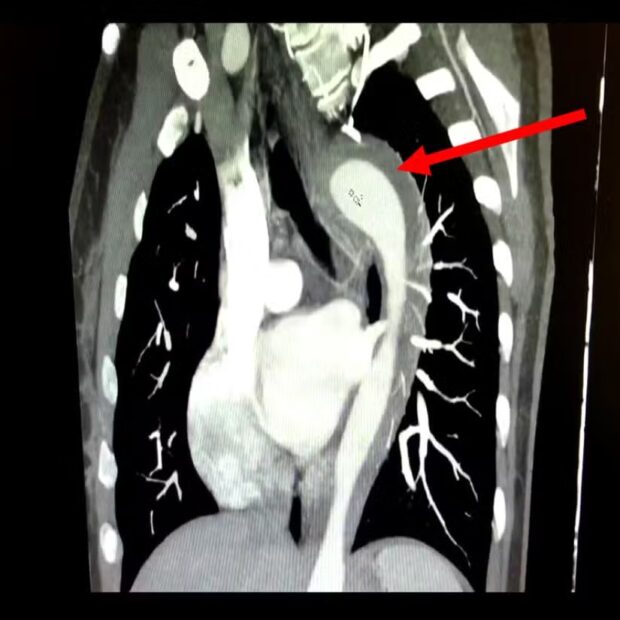

Acontece que, de acordo com informações do G1, uma mulher de 45 anos rompeu a aorta durante o ápice do prazer com o marido. Aos médicos, ela alegou sentir dores intensas, ‘como facadas’, no tórax após chegar ao orgasmo.

À emergência, a paciente contou que as dores dilacerantes começaram durante a relação com o marido. No momento em que atingiu o orgasmo, ela sentiu um forte estalo seguido de dores que iam até as costas.

Bem, segundo os médicos responsáveis pelo atendimento da mulher, foi constatado que ela não tratava a hipertensão há um ano e fumava há 17, fatores que, em parte, colaboraram com o rompimento da aorta.

O hematoma na aorta é grave e se não tratado corretamente pode evoluir para aneurisma ou ruptura total, que pode levar o paciente à morte. No entanto, o tratamento pode ser clínico ou cirúrgico, de acordo com a área afetada.

Sobre o caso, a mulher foi submetida a uma cirurgia cardiotorácica e recebeu alta médica após três dias de internamento.